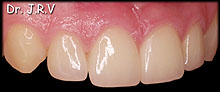

| Fotos 2A y 2B.- Imágenes de la sonrisa de una paciente

cuyos dientes presentan una tinción por tetraciclinas. |

| Fotos

2C, 2D y 2E.- Resolución del caso con la colocación de carillas

de porcelana de premolar a premolar. |